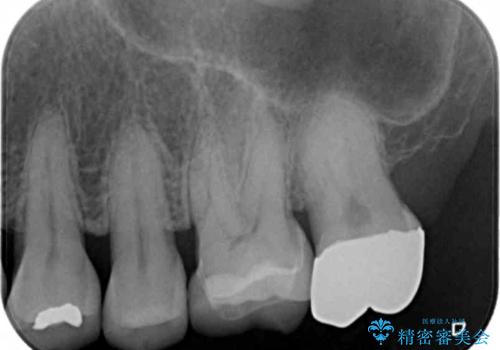

- 他院で装着した被せ物が割れたとのことで来院されました。

被せ物の厚みが確保されていなかったため、向かいの歯とのスペースを確保するように修正していきます。

被せ物の厚みが十分に確保できていないと、材料によっては今回のように割れてしまうことがあります。

被せ物の材料を変えるか、厚みを確保することでそのリスクを抑えることができます。

今回はセラミックでの再治療をご希望されたため被せ物の厚みを確保することで対応しました。

- 左上6/仮歯+ジルコニアクラウン:11,000円+110,000円費用は治療当時の料金となります